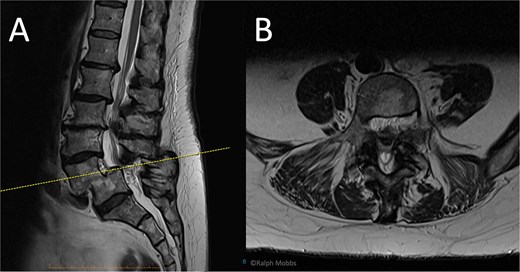

MRI revealed grade-II L4/5 spondylolisthesis with severe bilateral foraminal and lateral-recess stenosis, a lesser, left-sided L3/4 recess stenosis co-existed (Fig. 2). After shared decision-making, left-sided uniportal endoscopic decompression was performed under general anaesthesia, addressing L4/5. Critical stabilizers, the pars, inter-spinous ligament and majority of facet joints were preserved. No intra-operative complications, nor was instrumentation required.

Preoperative MRI of case 2. (A) Sagittal T2-weighted showing L4/L5 spondylolisthesis. (B) Axial T2-weighted.